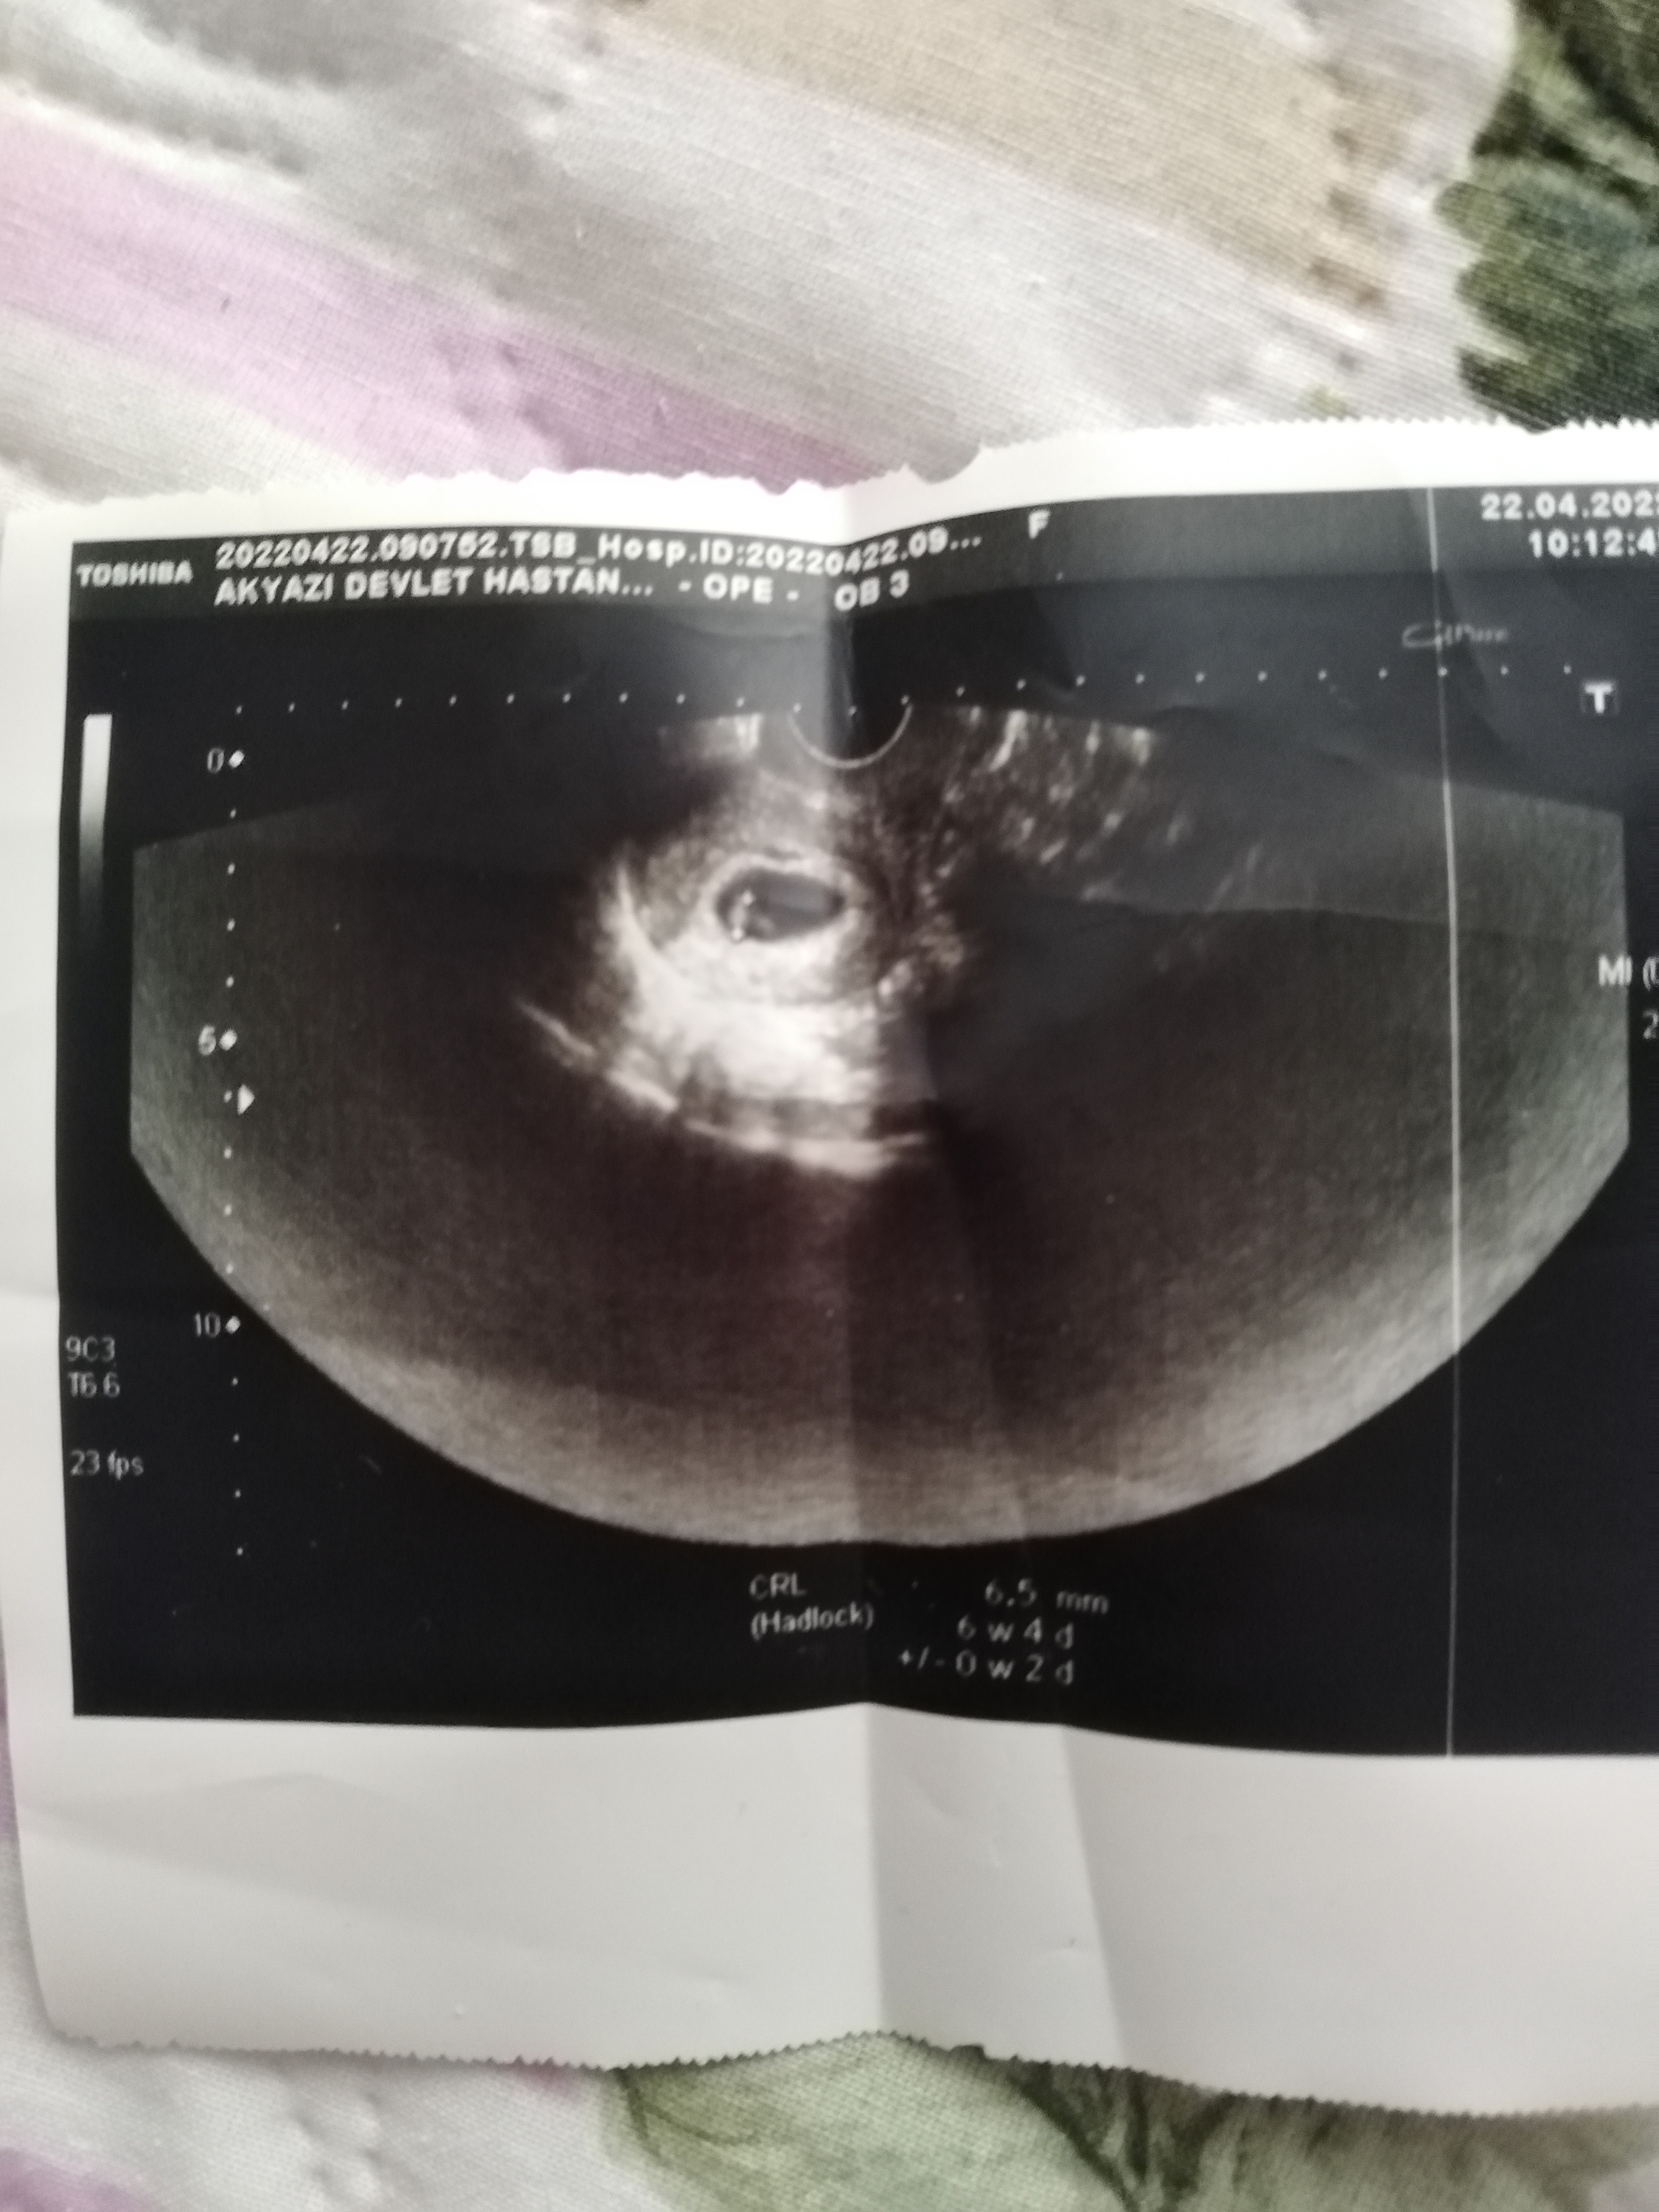

Canım bunlar Altan gözüktü sadece baş popo mesafesj var crl diye 6+4 pko olduğu için geç döllenme daha gitmedm doktora kalp atisii icin 7+7 yiz bugün

• IMG_20220429_113646.jpg

IMG_20220429_113646.jpg

2.6 MB · Görüntüleme: 179